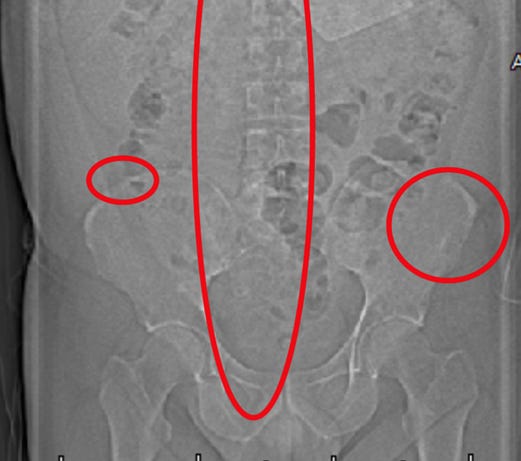

Mon patient a subi plusieurs examens d'imagerie révélant la présence de micropuces implantées. Ces emplacements correspondaient aux zones de torture les plus sévères. Ci-dessous, vous pouvez voir une micropuce entourée :

Il y en a un autre à la base du sacrum :

Une autre fracture est présente au niveau de la crête iliaque droite.

Le patient a subi un examen H-SCADA complet du corps, qui a permis de localiser les émissions de fréquences provenant des implants de microprocesseurs, également détectées lors des examens radiologiques. Le rapport explique que ces émissions indiquent la présence d'un capteur ou d'un dispositif électronique, dont plusieurs sont des semi-conducteurs.